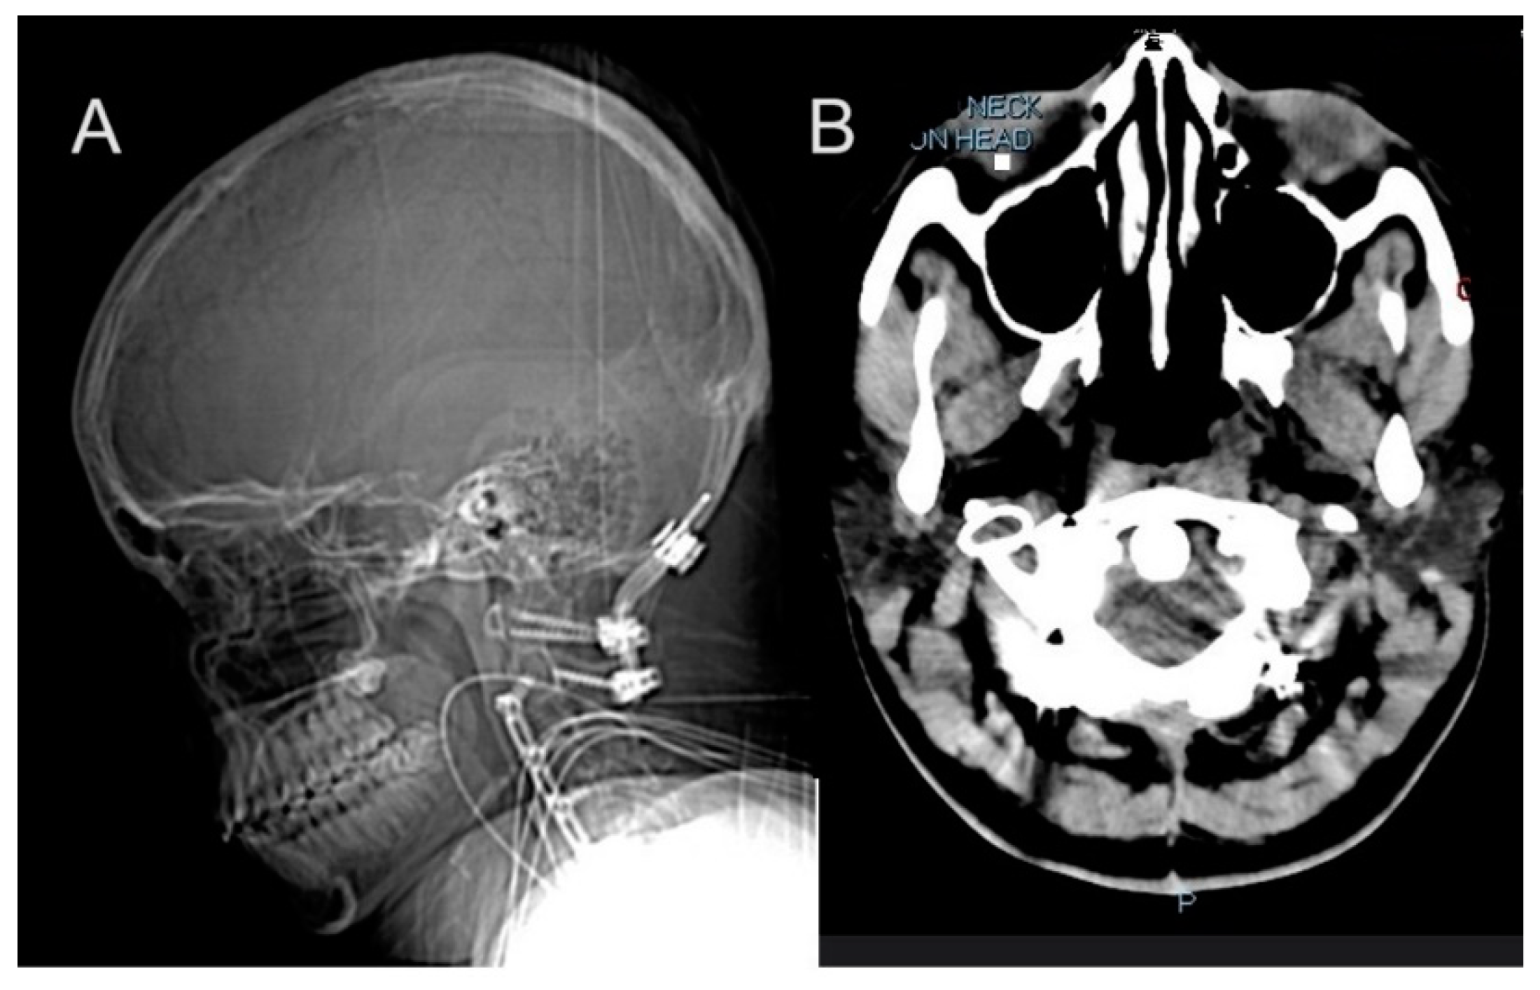

At age 12, she underwent tethered cord release surgery, which was complicated by multiple cerebrospinal fluid (CSF) leaks requiring blood patches and surgical revisions. This was followed by a series of spinal surgeries beginning with a skull-C2 fusion in 2013. Her vascular surgical history included multiple stenting procedures beginning in response to jugular vein stenosis, a condition linked to impaired blood flow from the brain with right internal jugular and transverse sinus stent placement. Despite these interventions, she continued to experience symptoms related to venous insufficiency and intracranial pressure. Idiopathic Intracranial Hypertension (IIH) management began at age 14 with initial ICP monitoring and lumbar shunt placement. This condition resulted in chronic headaches and required multiple surgical interventions. In 2014, she received a lumboperitoneal (LP) shunt placement, which was later removed in 2015 due to a crack in the tubing and followed by C2-C5 anterior cervical discectomy and fusion (ACDF) in 2015 (Figure 2A,B). This period also marked her initial diagnosis of pseudotumor cerebri. The following year, in 2016, she required left internal jugular stent for thrombus and obstruction, followed by superior sagittal sinus stent placement in 2017. These interventions were necessitated by recurring thrombosis and vascular complications associated with her hEDS. By 2019, further deterioration required additional surgeries including O-C7 fusion with removal of anterior hardware in June (Figure 2C,D) and C6/7 ACDF in December. Three separate repairs were required to address CSF leaks from the lumbar shunt removal site. The management continued to evolve, with additional procedures including sagittal sinus stent placement at age 17 and multiple VP shunt revisions.

Figure 2.

Longitudinal imaging findings in a patient with hEDS demonstrate progressive cervical spine instability and vascular complications. (A,B) A 2015 CT scan at age 15 showing post-surgical changes including occipital-C2 fusion and C2–C5 ACDF, with cervical lordosis straightening and C5–C6 anterolisthesis. Prior interventions included tethered cord release at age 12 and lumbar shunt placement at age 14 for IIH management. (C,D) CT in 2019 revealing expanded occipital-to-C7 fusion after hardware removal, necessitated by progressive cervical instability. (E) Brain MRI in 2016 demonstrates normal intracranial findings without restricted diffusion, hemorrhage, or tonsillar ectopia. (F) A 2016 angiogram showing asymmetric jugular veins with right-sided dominance, post-jugular foramen stenosis, and diminished left-sided flow.